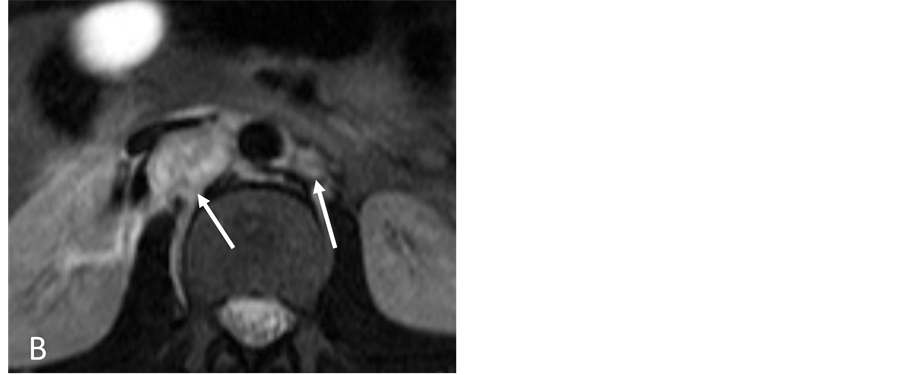

A 15-year-old man was referred to Interventional Radiology for evaluation of persistent retroperitoneal masses and hypertension with suspicion for renal artery stenos is. The past medical history was notable for a history of trauma and a retroperitoneal mass suspected to be a hematoma for a period of 5 years. Initial computed tomography (CT) scan demonstrated a low attenuation 1.6 cm × 1.5 cm retroperitoneal mass causing anterior deviation of the right renal artery suspicious for compression (Figure 1(A)). Renal ultrasound demonstrated normal kidneys bilaterally without signs of renal arterial stenosis. Further evaluation with magnetic resonance imaging (MRI)/magnetic resonance angiography (MRA) showed an irregular contrast enhancing 2.9 cm × 2.2 cm × 1.5 cm mixed signal retroperitoneal mass that demonstrated a mass effect on the inferior vena cava and right renal artery (Figure 1(B)). Despite elevated urine catecholamines, a subsequent iodine-131-meta-iodobenzylguani- dine (MIBG) scan was negative. Due to persistence of the mass and refractory hypertension requiring multiple antihypertensive medications, the patient was referred to Interventional Radiology for the evaluation ofsuspected renal artery stenosis.

Figure 1. (A) Contrast-enhanced CT scan section through the kidneys showing two retroperitoneal masses (arrows); (B) On MRI the lesions have high signal intensity on T2-weighted images (arrows). The right retroperitoneal tumor is located posterior to the IVC and right renal artery.